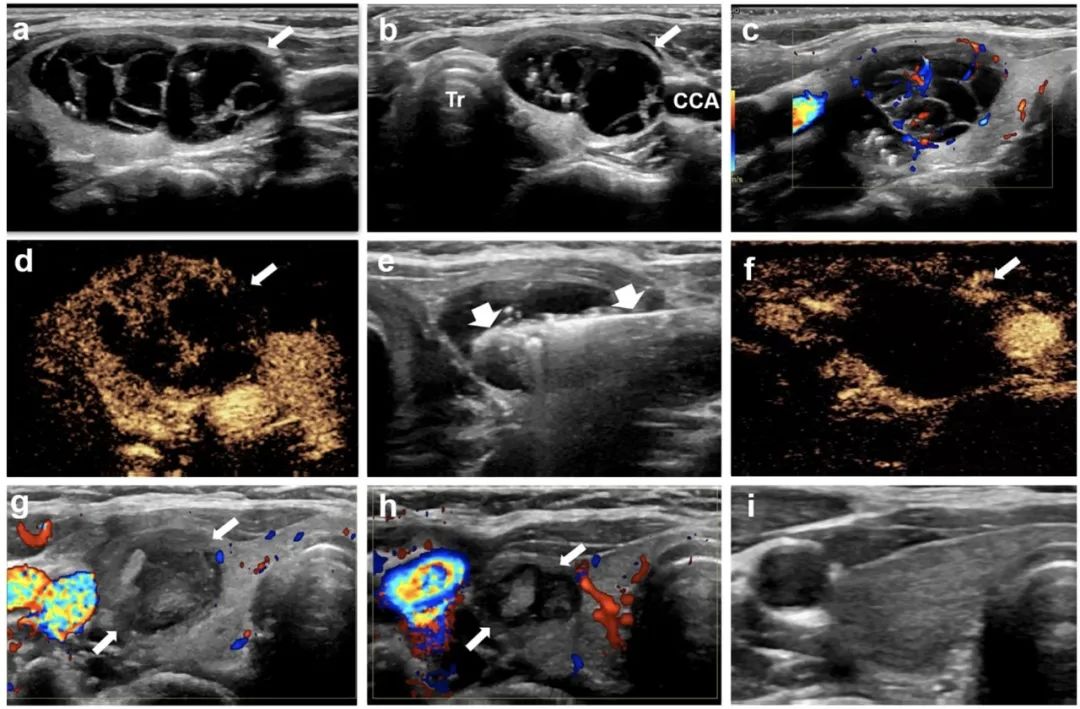

甲狀腺右葉囊性為主結節(jié),微波消融后3年,病灶完全消失